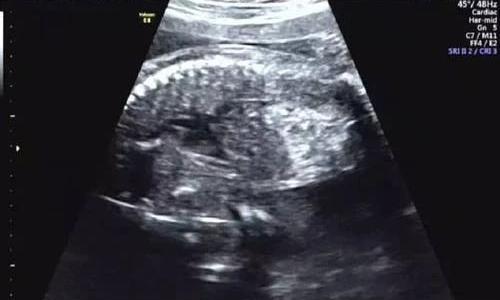

随着医学的进步和检查手段的提高,尤其产前B超的检查,使孕妈和宝宝都得到了很好保障,与此同时,有一些检查结果却给许多准爸准妈平添了很多烦恼,B超检查往往是困惑和纠结最多的一项产前检查,胎儿肠管回声增强就是其中之一,胎儿肠管回声增强原因是什么?今天我们就来讲一讲。

胎儿肠管回声增强指胎儿肠管局部或多发区域的回声强度接近甚至高于周围骨组织的回声强度。